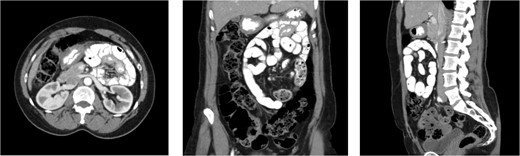

An 80-year-old female presented with symptoms of bowel obstruction. Her medical history was significant for hypertension, diabetes, and a total abdominal hysterectomy through a Pfannenstiel. She presented with ~1 day of colicky abdominal pain, nausea, vomiting, and denied previous episodes of similar symptoms. Physical exam revealed a soft but diffusely tender abdomen without peritoneal signs. Laboratory evaluation was significant for white blood cell count of 15 400 and a lactate of 3.6. A computed tomography (CT) scan of the abdomen was performed, which demonstrated a markedly dilated stomach and proximal small bowel, which was not the duodenum, in a retroperitoneal position. Images of the admission CT scan are depicted below (Fig. 3). Based on the concern for a paraduodenal hernia raised by imaging, as well as elevated white count and lactate, she was taken to the operating room for diagnostic laparoscopy which revealed that a majority of the jejunum was incarcerated within a left paraduodenal hernia. The bowel was reduced by gentle traction and found to be viable. The patient demonstrated evidence of chronic small bowel obstructions with several pulsion-type diverticula present due to recurrent episodes of occult obstruction. The mouth of the hernia defect, identified as Landzert’s fossa based upon its position at the base of the transverse mesocolon and nested between the proximal jejunum and the IMV, was closed with nonabsorbable suture. The operation was completed entirely laparoscopically with the patient experiencing no complications.

CT cross sectional images of Case 1, axial, coronal, and sagittal, respectively. Note the position of the dilated afferent small bowel (double arrow) posterior to the SMA (single arrowhead), thus confirming the retroperitoneal position of the entrapped bowel. Also note that while left paraduodenal hernias are typically described as existing in the left retroperitoneal position, there is no fixed midline barrier preventing their herniation to the across right of midline. In either case, the peritoneal defect, Landzert’s fossa, is the same with identical surrounding landmarks.